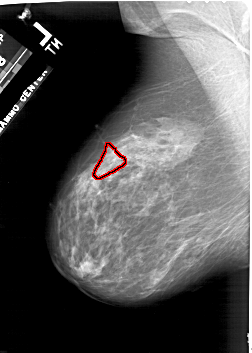

A_1941_1.RIGHT_CC

RIGHT_CC LINES 5326 PIXELS_PER_LINE 3751 BITS_PER_PIXEL 12 RESOLUTION 43.5 NON_OVERLAY